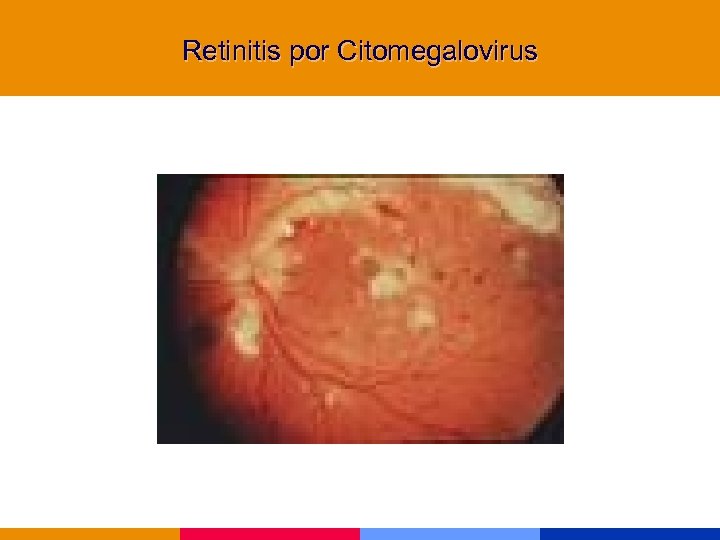

Infecciones por CMV § Afectan a pacientes severamente inmunocomprometidos § Afección de la retina, tubo digestivo, SNC y pulmón § Diagnóstico de retinitis: oftalmólogo entrenado

Infecciones por CMV § Afectan a pacientes severamente inmunocomprometidos § Afección de la retina, tubo digestivo, SNC y pulmón § Diagnóstico de retinitis: oftalmólogo entrenado

Retinitis por Citomegalovirus

Retinitis por Citomegalovirus

Retinitis por Citomegalovirus

Retinitis por Citomegalovirus

Retinitis por Citomegalovirus

Retinitis por Citomegalovirus

Retinitis por Citomegalovirus

Retinitis por Citomegalovirus